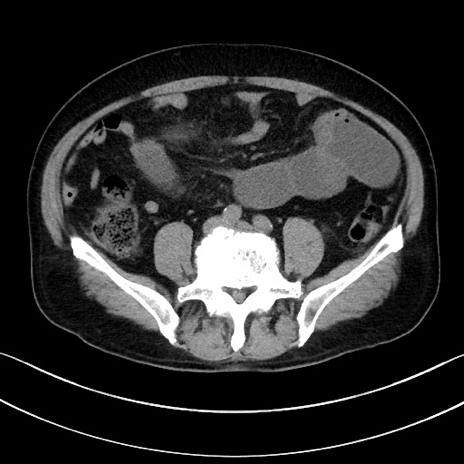

症例15(横断像)

【症例】70歳代男性

【主訴】腹痛

【現病歴】今朝から腹痛あり。全体的に痛い。特に左上の方。排ガスが今日はない。冷や汗が出る。

【既往歴】直腸癌術後

【身体所見】左側腹部〜上腹部に圧痛あり。腹膜刺激症状明らかなではない。軽度反跳痛。左下腹部に術後瘢痕あり。

【データ】WBC 7700、CRP 0.02